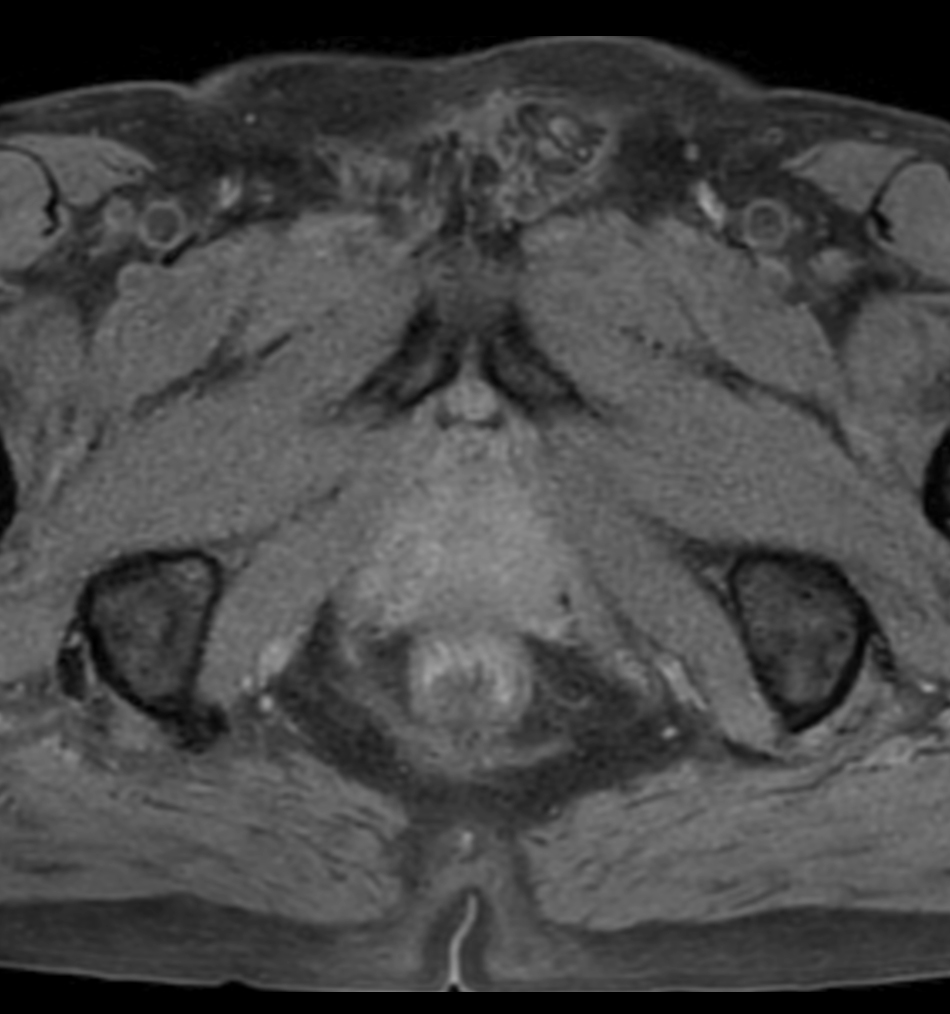

Prostate lesion with fat-free mDIXON XD imaging

Seirei Mikatahara General Hospital, Japan